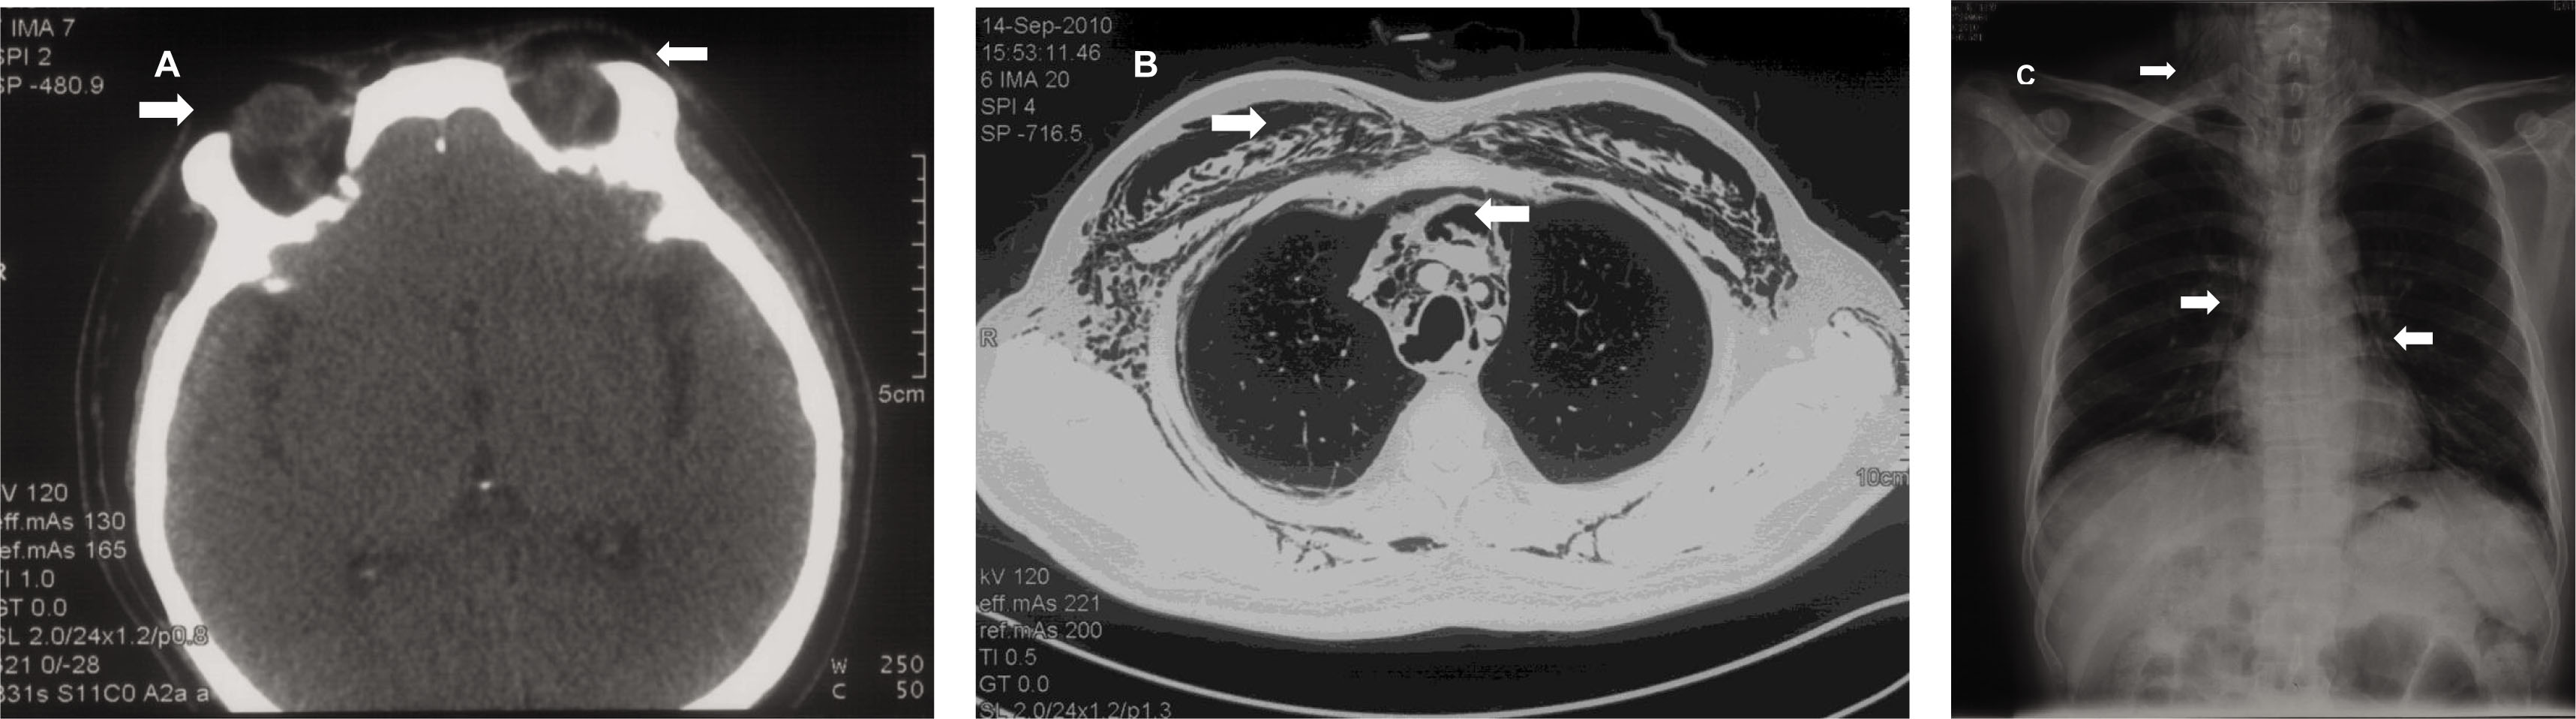

A 44-year-old man with a history of dermatomyositis presented to the clinic complaining of “swelling of the neck after a forced cough”. One month ago, he developed periorbital heliotrope rash and proximal muscle weakness. His serum creatine kinase level increased slightly (250 U/L), and his electroneuromyography showed myopathic abnormalities. The pathology of his right deltoid muscle biopsy revealed inflammatory myopathy with mild lymphocyte infiltration. A computerized tomography (CT) scan of the chest showed interstitial lung disease. A diagnosis of dermatomyositis was made, and the patient was given glucocorticoid and immunosuppressive therapy. Symptoms improved till several days ago when heavy cough developed and he felt a swelling neck. Physical examination revealed sub-cutaneous crepitation in the neck and chest wall. Chest X ray (Panel A) and CT scan (Panel B) confirmed pneumomediastinum (arrow) and subcutaneous emphysema (arrowhead). One day later, swelling and crepitation were also felt in his right eye lid. CT scan showed air in the periorbital and tempus region (Panel C, arrow). The patient was treated with methylprednisolone combined with cyclosporin and cyclophosphamide. There was complete resolution of the pneumomediastinum and subcutaneous emphysema 8 weeks later.

Panel A: A chest X ray demonstrated signs of pneumomediastinum (arrow) and subcutaneous emphysema (arrowhead) for this patient with dermatomyositis. Panel B: A Chest CT scan demonstrated signs of pneumomediastinum (arrow) and subcutaneous emphysema (arrowhead) for the patient with dermatomyositis. The bilateral lung fields were otherwise clear. Panel C: On a head CT scan, air was identified in the periorbital and tempus region (arrows).